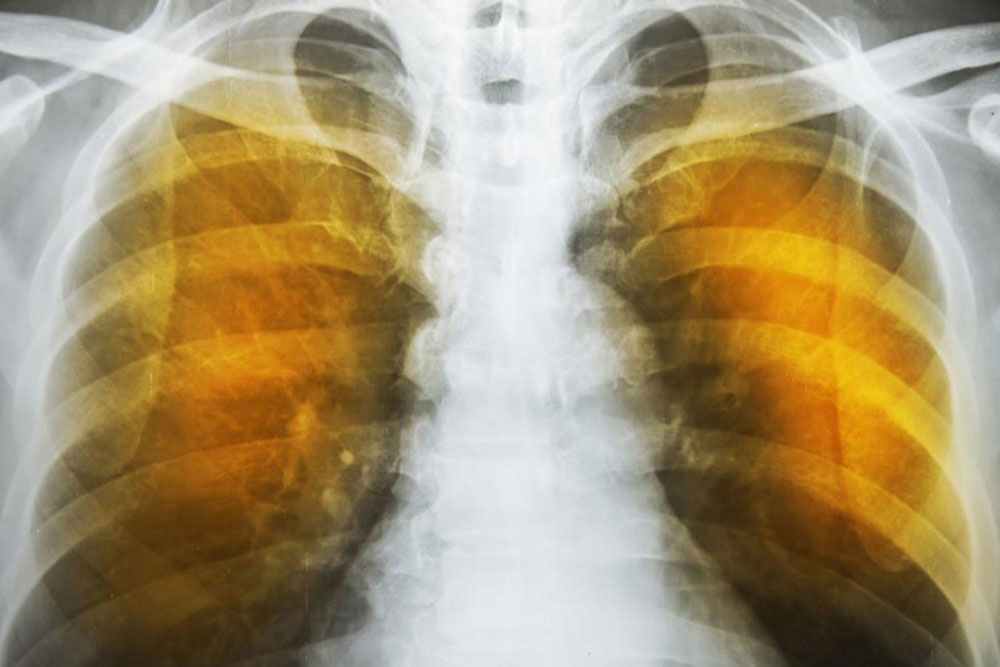

The symptoms of emphysema are exceedingly severe and cause considerable damage to the lungs before the symptoms even show up. Generally, one feels a lack of energy and the tendency to skip some of the common daily routines.

As the deterioration continues, the alveoli lose their strength and start rupturing. In extreme cases, there may be large scale destruction which leads to empty spaces in lungs called bullae. This would reduce the functional area of the lung which in extreme cases call for surgical removal. In an extremely rare condition, large scale rupture of alveoli can cause a condition called pneumothorax and the collapse of the lung, a very serious condition, which can be fatal. The best thing one can do is stop exposure to irritants.